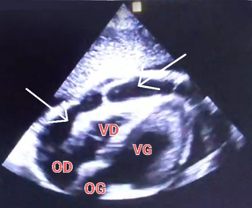

The patient presented to the emergency department with acute left lateral chest pain, worsening on inspiration and in a supine position. She also had a recent flu-like illness. Physical examination revealed an apyretic patient who was tachycardic at 100 bpm, with BP of 170/100 mmHg; eupneic, with SpO2 of 98% on room air; with pericardial rub on auscultation; and with no signs of overload. The electrocardiogram (ECG) showed no ST segment or PR interval abnormalities. Chest X-ray revealed cardiomegaly (Figure 1).

Figure 1.(A) Chest X-ray from 2021. (B) Admission chest radiograph showing cardiomegaly (cardiothoracic index 0.8).